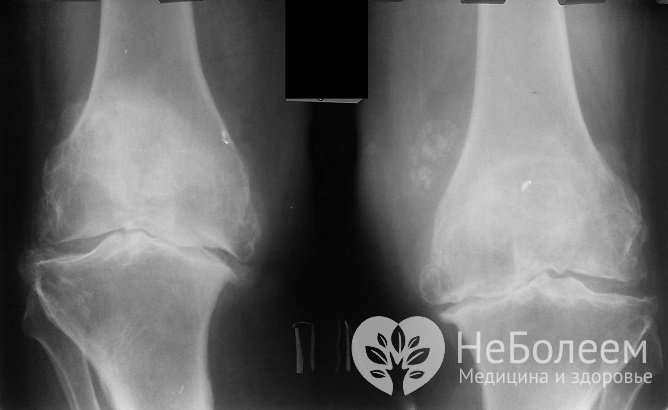

Основным инструментальным методом диагностики при артрите коленного сустава является рентгенография. Исследование проводится в 3 проекциях: прямой стоя, боковой лежа с согнутым суставом на 20–35°, аксиальной (вдоль длинной оси). Существует ряд специфических критериев, подтверждающих наличие заболевания:

Рентгенография при артрите коленного суставаПомимо рентгенографического исследования для подтверждения диагноза также используются следующие методы: